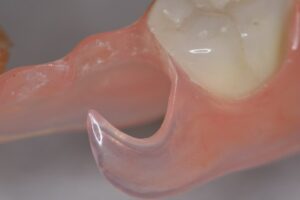

テレスコープ義歯とは──残った歯を守る発想

ここからはテレスコープ義歯の話です。テレスコープ義歯は、クラスプ義歯とは全く逆の発想で作られます。まず歯を加工して金属の「茶筒状のキャップ(内冠)」で包み、その上に外冠と呼ばれる義歯本体を精密に重ね合わせます。装着後は、歯と義歯が一体化するように設計されているのです。

この構造により、噛む力は歯が最も強いとされる上下の歯軸方向にだけ伝わります。硬い食べ物でも力が分散され、歯や歯ぐきに無理なく伝わるため、歯への局所的な負担が小さくなります。着脱も歯軸方向に沿った動きなので、横揺れを生じにくく、歯にかかる力が安定するのです。これが「リジッドサポート(剛性支持)」という考え方です。

当初は保険のクラスプ義歯を入れていましたが、動いて痛く、しっかり噛めないという訴えがありました。インプラントは希望されなかったため、テレスコープ義歯に変更。結果として右側でも硬いものが噛めるようになりました。写真の左は外したところ、右は装着したところです。手前2本の歯に内冠を作り、セメントでかぶせてあります。

この内冠に合わせて外冠が作られ、外冠の内面にはPEEK(ポリエーテルエーテルケトン)という耐久性の高い樹脂が貼られています。これが維持装置として働きます。